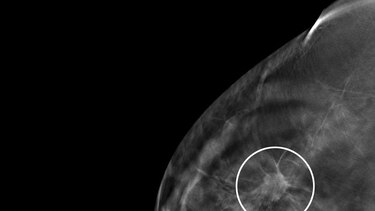

En el caso del cáncer de mama, Panamá sigue patrones de países no desarrollados en cuanto a la mortalidad. “Vemos mayor incidencia (porque hay más tamizaje), pero la mortalidad va subiendo”, dice Motta.

Al margen de la controversia que ha existido por años sobre la efectividad de las mamografías, Motta destaca que en las provincias y áreas remotas el acceso a una mamografía no es tan fácil, y cuando se hace un diagnóstico tarde, cuando ya la mujer tiene metástasis, la probabilidad de sobrevivencia se reduce. “Creo que es un efecto de inequidad y diagnóstico tardío”.

Al respecto, el oncólogo médico Juan Pablo Barés, presidente de Fundacáncer y otro de los autores de este trabajo, señala que faltan más datos para investigar a fondo el cáncer de mama. “No tenemos elementos importantes, por ejemplo, ¿cuántos pacientes de cáncer de mama, en diferentes estadios, se han detectado en el país? Tenemos un subregistro”.“Contamos con las mismas herramientas de tratamiento de países desarrollados, en Panamá hay excelentes cirujanos, oncólogos médicos, radiooncólogos, medicinas, etc., ¿por qué no vemos una reducción en la mortalidad?

Uno de los aspectos que resalta, y en eso coincide con Motta, es que no todas las pacientes tienen el mismo acceso a la tecnología de diagnóstico. “En Panamá no en todos los lugares hay mamógrafos. No en todos los lugares donde los hay se encuentra un especialista para interpretar las mamografías. Y no en todos los lugares se le puede hacer una biopsia expedita a las pacientes. Puede tomar un mes, tres meses. Todo esto afecta el diagnóstico”.